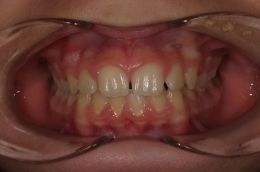

.... Spontaneo riposizionamento dei molari permanenti! Dopo 8 mesi viene tolto il REP! Contenzione con dispositivo elastodontico che guida in eruzione i denti permanenti! Durata: 24 Mesi Inizio Aprile 2006 - Fine Aprile 2008 A fine terapia si cerchera' di evitare un trattamento ortodontico fisso, se cio' sará possibile, finalizzando il caso con un positioner individualizzato!